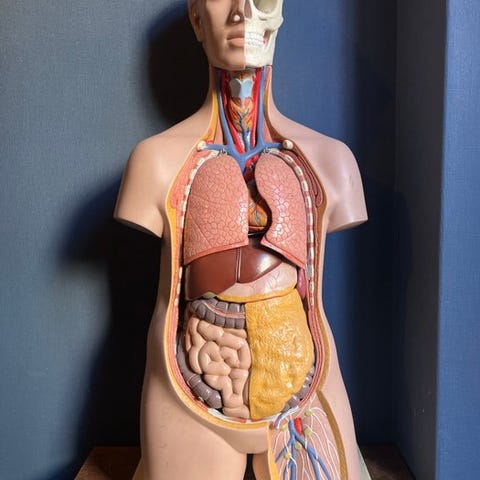

Anatomisk model - Plast - 1990-2000 - Rygsøjlen og hofterne

Plastik kolonne-model i naturlig størrelse, 83 cm høj, 30 cm bred og 20 cm dyb, fra ca. 1990–2000, i god brugt stand med mindre aldersmærker og pletter, i funktion og monteret på en høj kvalitet jernbase. Klik på den blå "gå til varen" knap, for at købe eller byde på denne vare. Den samlede pris vil blive vist inden du afgiver dit bud.

Denne 1:1-naturlige størrelse hvirvelsøjlemodel på 83 cm viser i detaljer alle hovedtræk ved hver hvirvelsøjle, herunder rygraden, nervetråde (nerverødder), vertebrale arterier, intervertebrale skiver, tværgående processer og snit af rygsøjlen. Forskning og studier

Modellen er særligt egnet til visning af en række patologiske misdannelser (rygsøjlens scoliose, lordose, kyfose). Der vises også føle- og spinalender. Den står på en basiskonstruktion. Så kan du levende forklare relevante kundskaber for eleverne gennem modellen, få eleverne til at forstå og hurtigt mestre